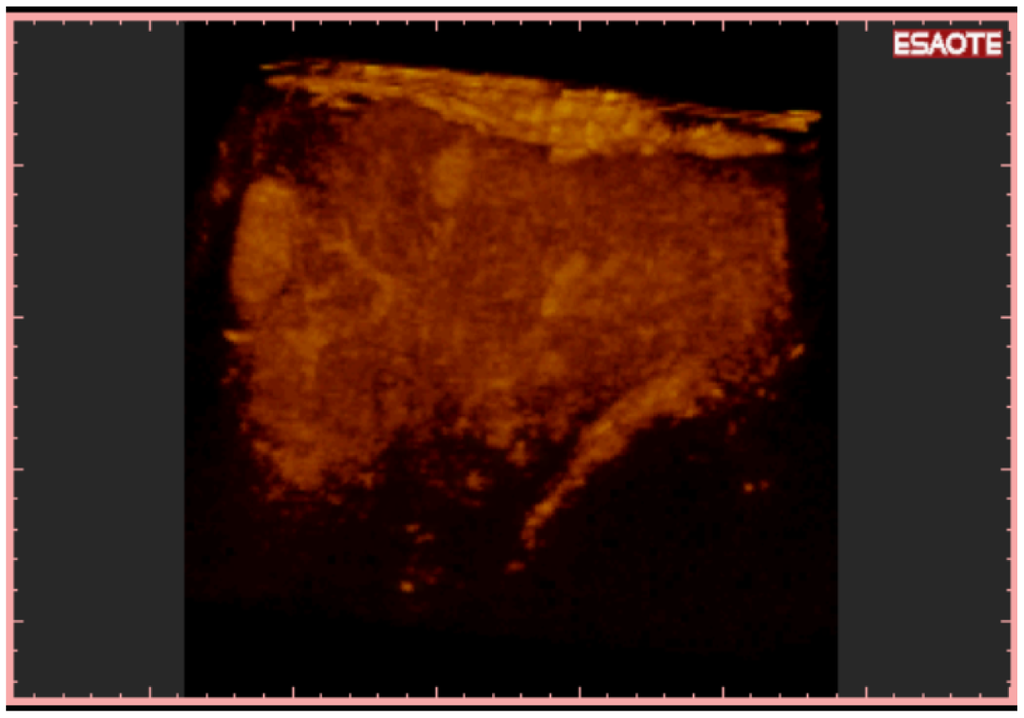

To easily perform a 3-D reconstruction of a 2-D acquisition of CEUS imaging of the whole liver, the 2-D acquisition is performed with real time scanning perpendicularly on the long-axis of the liver, for a complete 2-D image of its short-axis (Figure 2). The subsequent reconstructions of these planes show a rendered volume with a “parenchimal” aspect (Figure 5) or with a “vascular” map (Figure 6) of all the hepatic segments with an acquisition in the early arterial and in portal phase.

3-D NAV CEUS correctly detected all the local recurrences, 92/98 (93.87%) of new nodules (Figure 7) and 26/28 (92.8%) multinodular HCC (Figure 8 and Figure 9) (the same patient with small multinodular HCC false negative also for spiral CT). Dimensions of eight false negative for 3-D NAV CEUS were: Six nodules less than 2 cm, two 3 cm; their segmental distribution was: Four nodules in segment IV and four nodules in segment VI. In two cases 3-D NAV CEUS erroneously diagnosed an artero-venous malformation as new HCC (false positive) (confirmed by MRI and follow-up).